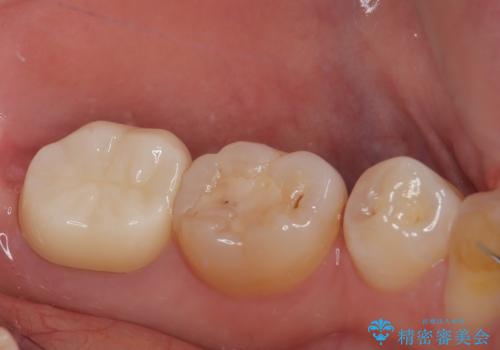

歯茎の治癒を3か月程度待ち、最終的なフルジルコニアクラウンの形に整え精密な型どりをシリコーン印象材にて行っております。

精密印象時、舌がよく動いたり唾液の量も多かったため個歯トレーを使用しています。